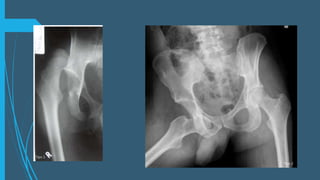

Valoración de imagen

Proyección anteroposterior

de la pelvis

En una AP: observar la línea

de Shenton continua y

regular.

Hay que valorar el cuello del

fémur para descartar una

fractura antes de realizar

maniobras de reducción .

La proyección oblicuas a 45°

(Judet) son útiles para valorar

si hay frag. Osteocondrales ,

el acetábulo y fx de femur.

Tras la reducción se toma

una TC.

La RM útil para valoración

del cartilago articular y

vascularización

Valoración de imagen Proyecciónanteroposterior de la pelvis En una AP: observar la línea de Shenton continua y regular. Hay que valorar el cuello del fémur para descartar una fractura antes de realizar maniobras de reducción . La proyección oblicuas a 45° (Judet) son útiles para valorar si hay frag. Osteocondrales , el acetábulo y fx de femur. Tras la reducción se toma una TC. La RM útil para valoración del cartilago articular y vascularización